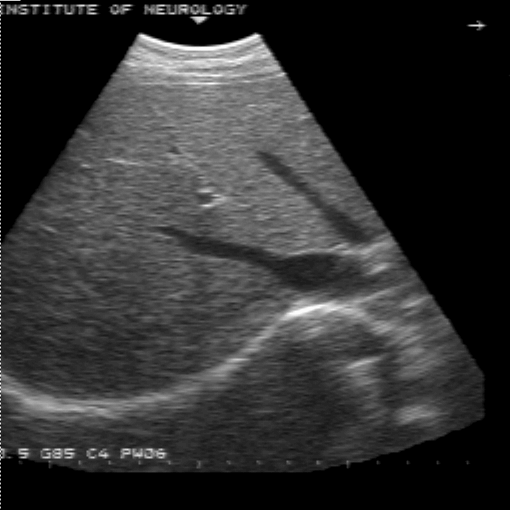

Для решения данных проблем разработана следующая схема передачи данных из ультразвуковой медицинской диагностической установки в персональный компьютер. (плакат 1) Я осуществлял подключение ультразвуковой диагностической установки ALOCA SSD 650. Она осуществляет срез информации органов исследуемого пациента на глубину до 30 см. от места контакта с телом пациента и работает на частоте от 2 до 7,5 мГц. И выводит информацию на экран с разрешением 640 * 480 с 64 уровнями градации серого. Полученная информация преобразуется в стандартный видеосигнал, который может быть снят с специализированных выходов. Захват и обработку информации из ультразвуковой медицинской установки осуществляется устройством, называющимся frame grabber. Оно позволяет в «реальном времени» преобразовать видеосигнал в цифровое изображение и сохранить его в персональном компьютере. К frame grabber’у предъявляется ряд характерных требований. Это должно быть устройство, позволяющее длительную оцифровку видеосигнала в реальном времени, обладать высокоскоростной «шиной», для быстрой передачи полученной информации в персональной компьютер. В нем должна быть предусмотрена возможность настройки яркости и контрастности для первоначальной настройки при подключении к медицинской диагностической установке и оно должно быть совместимо со всеми основными современными операционными системами. Всем этим требованиям удовлетворяет frame grabber HI*DEF PLUS фирмы IMAGRAPH. Данный frame grabber позволяет получать 256 уровней градации серого, что позволяет иметь запас по разрешению изображения для ультразвуковых медицинских установок более высокого класса и получать изображения, над которыми можно производить определенные операции. Кроме того, это сравнительно недорогое устройство, в своем классе, что является преимуществом, т.к. наши медицинские учреждения финансируются не достаточно. Frame grabber передает информацию в передает информацию в персональный компьютер первичного пользователя. Оптимальной конфигурацией персонального компьютера первичного пользователя является P2 – 400, 128, 4.3 + 18 SCSI, 8 V I740. Данная конфигурация предоставляет возможность осуществлять захват изображения из ультразвуковой медицинской диагностической установки, поддерживать режим телеконференций, осуществлять передачу получаемого сигнала по сети в реальном времени и обрабатывать получаемую информацию. Но т.к. парк персональных компьютеров в медицинских учреждениях России, на данное время, состоит из персональных компьютеров устаревших моделей, то в этом случае можно использовать лишь основные функции - захват и обработку изображений. Это можно осуществлять на персональных компьютерах класса DX4 – 100 с 16 мБ оперативной памяти, размером жесткого диска 800 мБ и сетевой картой NE2000 или совместимой. Персональный компьютер первичного пользователя позволяет передавать полученную информацию по компьютерной сети. Вопросы передачи информации по компьютерной сети подробно рассматриваются в дипломном проекте Еремеева Артема, который также выполнял дипломную работу в рамках проекта «телемедицина». К персональному компьютеру вторичного пользователя предъявляются те же требования, что и к персональному компьютеру первичного пользователя, за исключением того, что у в нем не устанавливается frame grabber для захвата изображения с ультразвуковой медицинской диагностической установки. В результате захвата изображения получается файл в котором необходимо отобразить не только информацию собственно о картинке, но и дополнительную. Для этого был разработан формат файла плакат 2 , который содержит в себе следующие поля:

Информационное поле данного файла на прямую связано с характеристиками ультразвуковой медицинской диагностической установки, frame grabber’а и персональным компьютером. В рамках данной работы, в результате взаимодействия с медицинским персоналом, возникла необходимость преобразования изображений для выделения областей, контуров этих областей, границ образований. Для этого мною были внедрены ряд фильтров. Это сглаживающий фильтр, медианный сглаживающий фильтр, контурный фильтр и полутоновой фильтр. Результаты воздействия данных фильтров на изображение можно наблюдать плакат 3. По результатам консультирования с врачами, было выявлено, что их применение дает наиболее хороший эффект при последовательном воздействии на изображение нескольких фильтров. Это можно наблюдать на плакате 4. Это было апробировано специалистами и было выявлено, что результаты воздействия этих фильтров на изображение несут в себе высокую практическую ценность. В данной дипломной работе было: